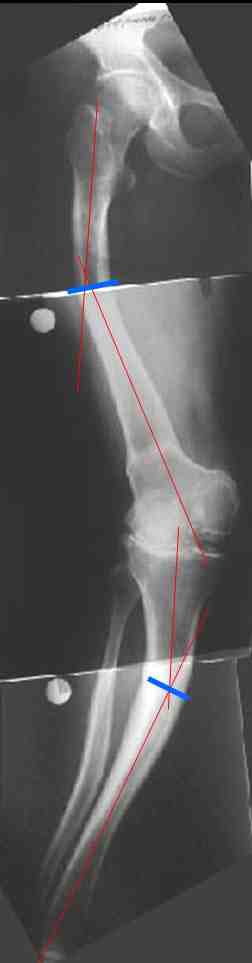

В данном случае перед эндопротезированием мы бы корригировали оси бедренной и большеберцовой костей (см. вложение). Дистальный эпидиафизарный угол бедра будет корригирован при эндопротезировании. Тип остеотомии и коррекции деформации (клиновидная резекция - одномоментная коррекция; формироване треугольных или трапециевидных регенератов во времени) - исходя из

относительной длины конечности.

На бедре дистальный отдел в сгибательной установке после, видимо, когда-то сделанной корригирующей остеотомии. Не надо ли на том же уровне все-таки "разогнуть" бедро до протезирования? Сам протез, наверно, можно поставить в большем или меньшем "сгибании", но весь дистальный эпиметафиз бедра и все нижележащее оказывается кзади от механической оси бедра. Насколько это допустимо, не ведет ли к расшатыванию протеза? Или можно как-то рассчитать такой наклон протеза, что он компенсирует это смещение?

И нет ли смысла аппаратом исправить не только кривые диафизы, но и взимоотношения собственно суставных концов бедренной и большеберцовой костей, они ведь там контактируют с вальгусом градусов 25? Это позволит дозированно удлинить мягкие ткани по латеральной стороне.

Это один из самых сложных вариантов для эндопротезирования, т.к. мы имеем деформацию бедренной кости в трех проекция, думаю, что есть и

ротационная деформация, плюс к этому - деформация голени. Однозначно в таких случаях, в отличии от возможностей при эндопротезировании ТБС необходимо выполнить корригирующие остетомии на двух уровнях. Что касается сгибательно установки мыщелков бедра - думаю, что это не является проблемой, особенно если на операции будет испрользован заднестабилизированный протез. Относительно вальгуса - все не так однозначно - возможно, что деформация слегка преувеличена за счет проекционной установки из-за ротационной деформации. Поэтому планирование операции необходимо будет делать только после коррекции деформации.